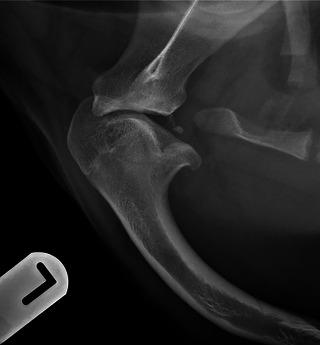

Two skeletally immature female dogs were each investigated for chronic weight-bearing thoracic limb lameness. The first patient was lame for 2 months following a tumble whilst playing, and the second patient had been intermittently lame since 3 weeks of age. In both cases, radiographic examination of the shoulder revealed fissuring of the caudal humeral head consistent with an incomplete proximal humeral Salter-Harris type IV fracture with an Enoki-mushroom-like appearance of the caudal fragment, where two heads rise from a common stem. There was secondary neoarthrosis of the caudal humeral head fragment with the glenoid rim of the scapula. Humeral head-split fracture is an unusual fracture pattern that rarely occurs in skeletally immature patients, and conservative management appears to result in reasonable short-term outcomes. The role of early detection and surgical intervention remains unknown.

两只骨骼未成熟的雌性犬因慢性负重性前肢跛行接受了检查。第一只犬在玩耍时摔倒后跛行2个月,第二只犬自3周龄起就间歇性跛行。在这两个病例中,肩部的X线检查显示肱骨头尾部有裂隙,符合肱骨近端Salter-Harris IV型不完全骨折,尾侧骨折块呈金针菇样外观,即两个“头”从一个共同的“柄”上长出。肱骨头尾部骨折块与肩胛骨关节盂边缘出现了继发性假关节。肱骨头劈裂骨折是一种不常见的骨折类型,很少发生在骨骼未成熟的患者中,保守治疗似乎能带来合理的短期预后。早期检测和手术干预的作用尚不清楚。